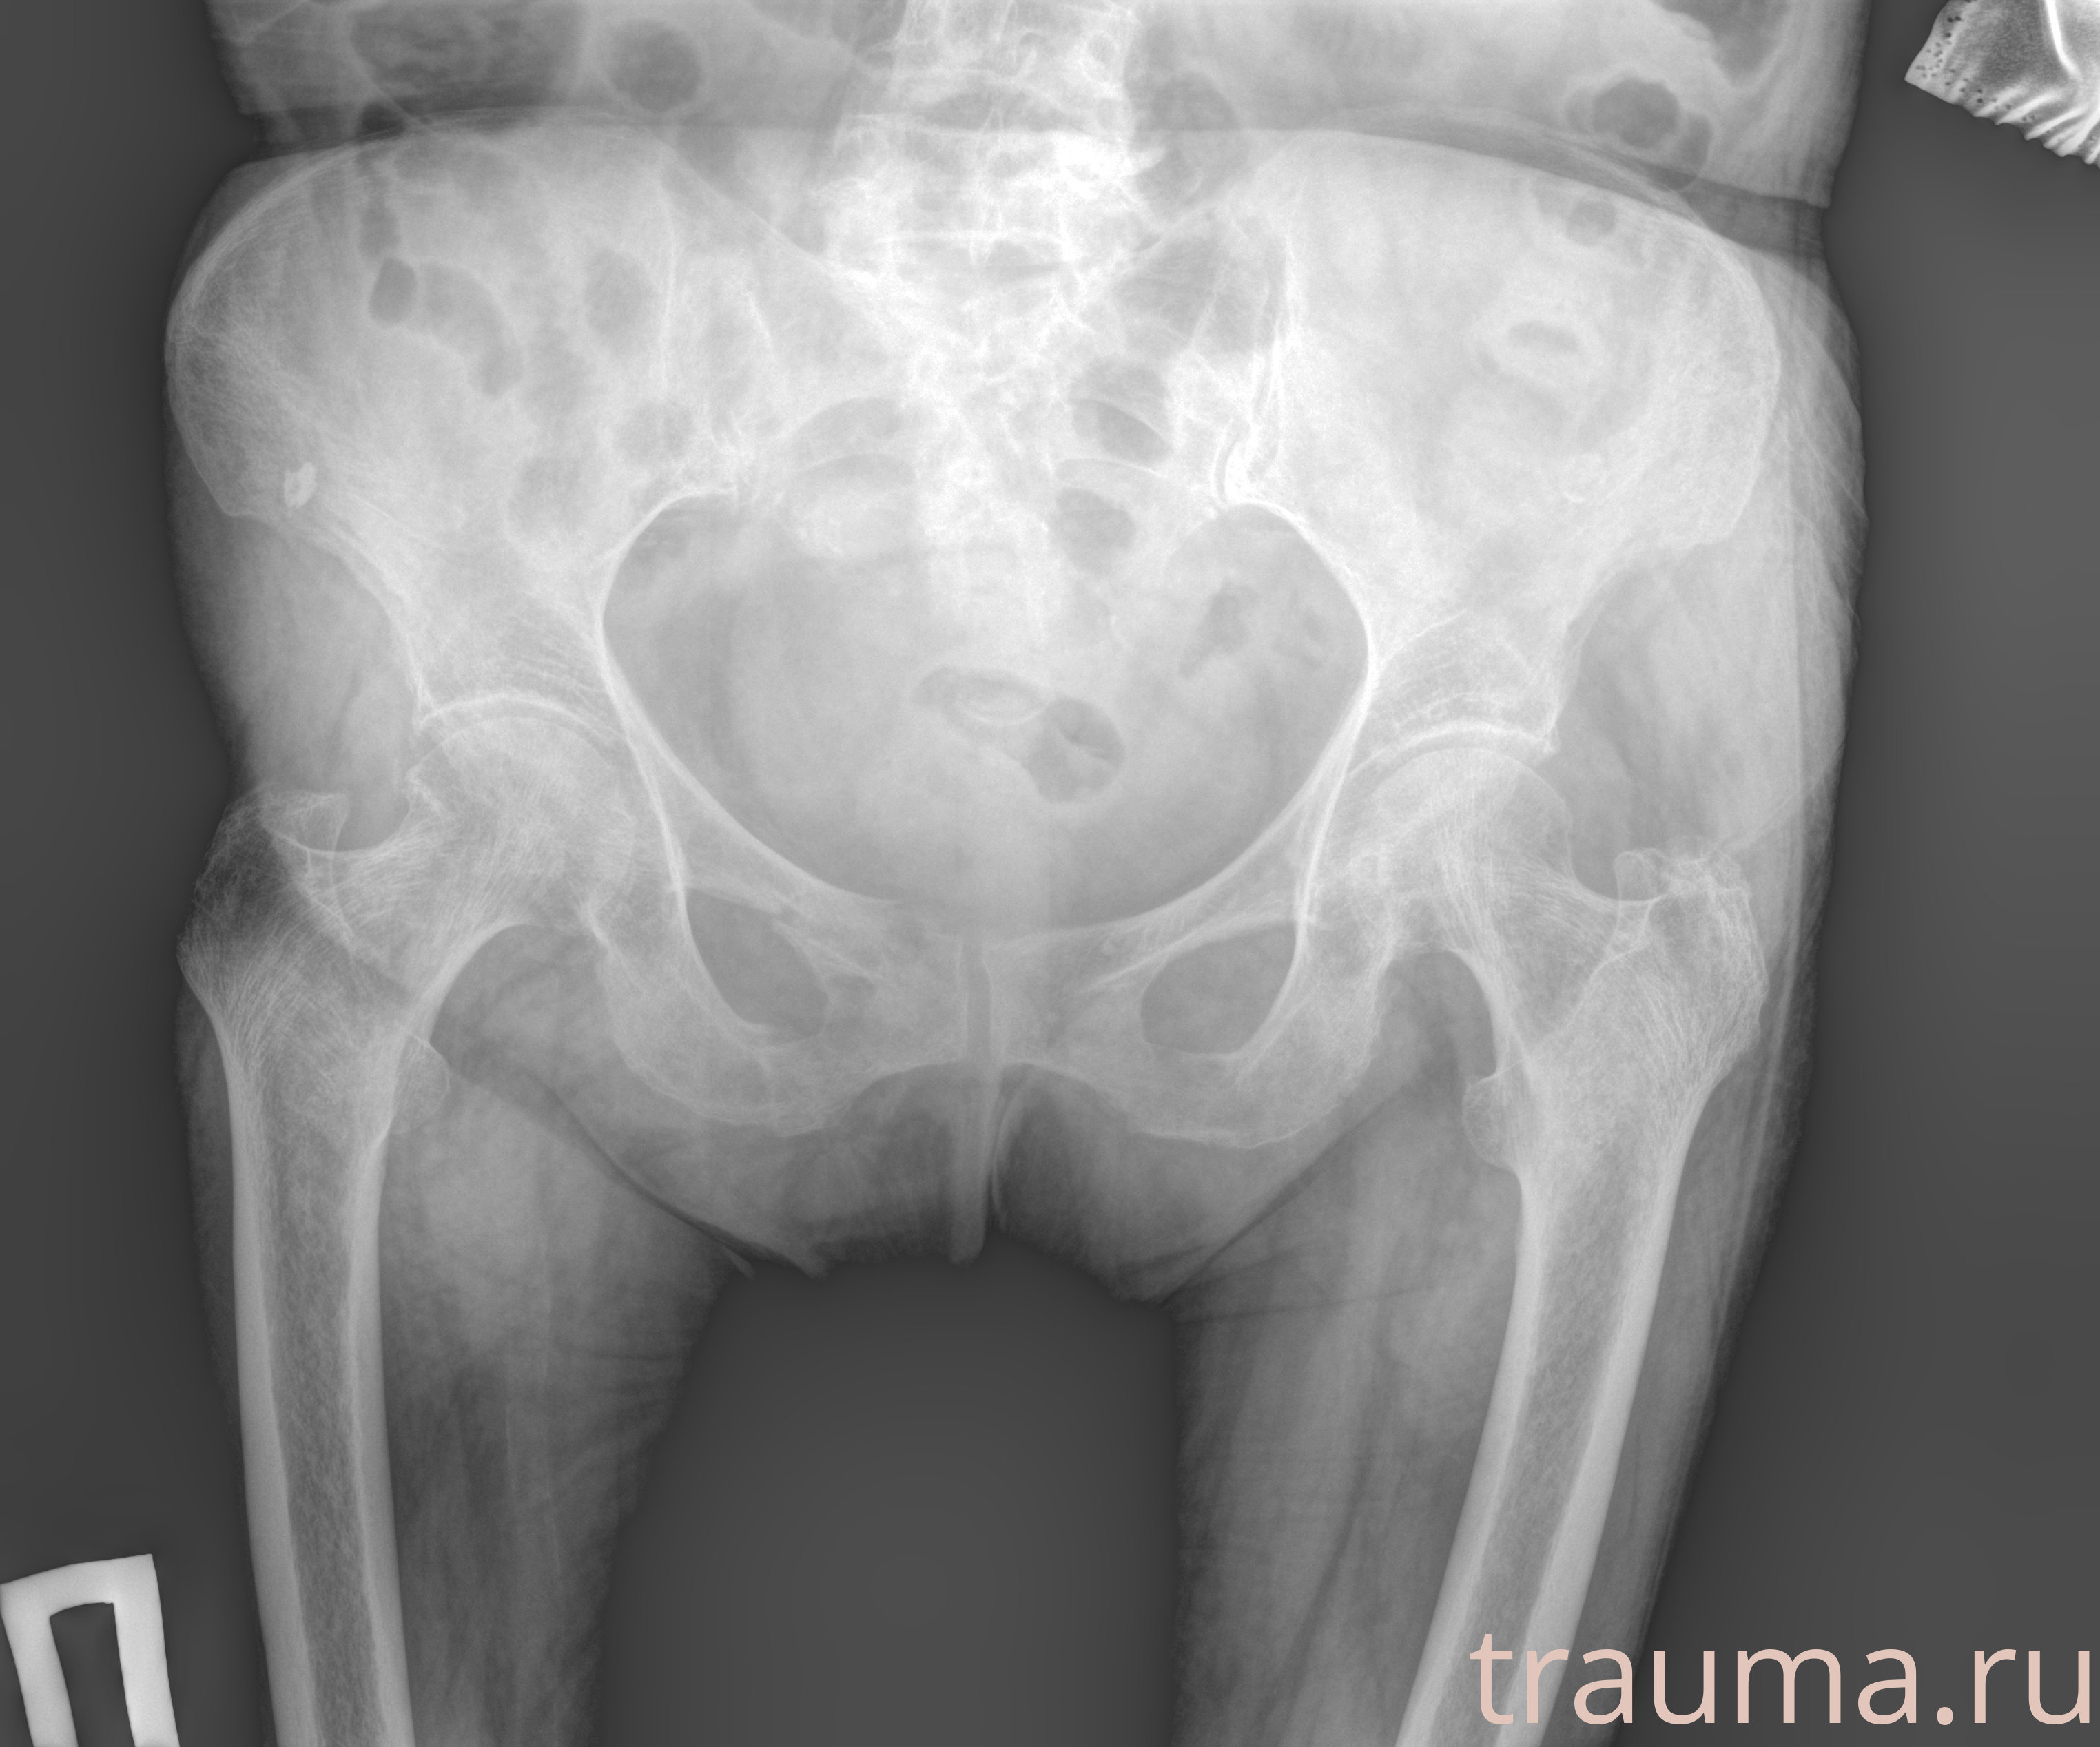

Первая помощь при переломе шейки бедра

Рентген на дому: по вашему адресу приезжает врач-рентгенолог, травматолог-ортопед с мобильным рентгеновским аппаратом, проводит диагностику травмы или заболевания, делает необходимые рентгенограммы, дает рекомендации по дальнейшему лечению. Получить качественные снимки в домашних условиях возможно благодаря уникальной методике, разработанной МосРентген Центром для института  Склифосовского